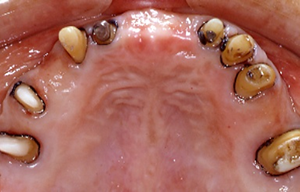

初診時

最終的な上顎の土台の歯の状態と補綴物です。

矯正治療により支台歯の方向を調整します。